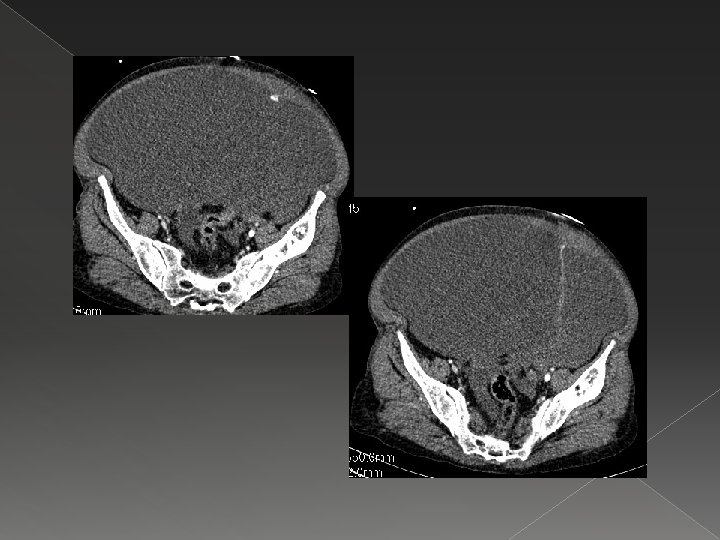

Malign Asit � Tanım: Peritoneal kavitede kanser kaynaklı anormal sıvı toplanması. � En sık sebepler meme, akciğer, over, mide, pankreas, kolon kanseri ve mezotelyomadır (Becker et al. 2006). � Yüksek volümde asit sıvısı abdominal basıncı artırır ve nefes darlığı, şişkinlik, bulantı, iştahsızlık, asit reflü, hareket kaybı , alt ekstremite ödemi ve fiziksel görünümden dolayı moral bozukluğu gibi semptomlara yol açar. � Malign asit gelişimi sonrası ortalama yaşam süresi 1 -4 aydır. Palyatif tedavi alan hastalarda yaşam süresi uzayabilir (Courtney et al. 2008). � Medikal tedavi (diüretik, tuz kısıtlaması) yararsızdır.

Malign Asitte Palyasyon � Yüksek volümlü parasentez � Tünelli peritoneal kateter � Peritoneal port-kateter � Peritoneovenöz şant › Perkütan drenaj kateteri (sınırlı endikasyon)

Parasentez � Semptomatik hastada ilk seçenek. � Bir defada 3 -4 litre sıvı alınabilir. Eksudatif nitelikte olduğu için hipovolemi ve böbrek yetmezliği riski daha az. 3 -4 litre için plazma ya da albümine gerek yok. � Sık tekrarlayan parasentez ile protein kaybı görülebilir. � Kanama parametreleri konusunda çok rijid davranmaya gerek yok.